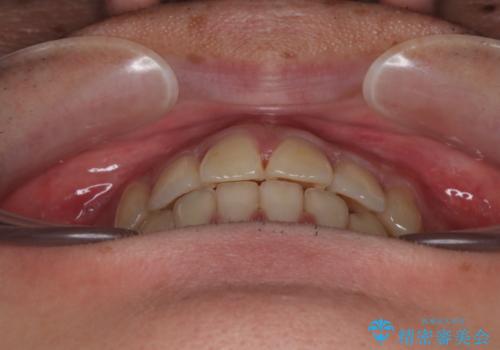

- 高校生の時に行った抜歯矯正の後戻りを気にして来院された患者様です。

インビザラインでの治療を希望されていて、デコボコの程度が中等度であり、安価なパッケージにて対応可能と判断されたため、インビザライン・モデレートを用いて矯正治療を行うこととしました。

インビザライン・モデレートは、製作できるアライナーの枚数に制限があるため、移動可能な量に限りがあるものの、インビザライン・ライトよりも枚数が多いため、幅広い症例に対応可能です。